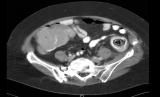

Plain radiographs of the abdomen reveal a nonspecific bowel gas pattern with scattered air-fluid levels and phleboliths in the lower pelvis. A CT scan of the abdomen and pelvis demonstrates a soft tissue mass with an eccentrically placed fatty area (stranding) in the descending colon (Figure 1). Images from a Gastrografin enema indicate a possible intussusception in the sigmoid colon. Flexible sigmoidoscopy reveals a lesion that obstructs the lumen at the splenic flexure (Figure 2).

En block surgical resection is chosen because of the lesion seen on CT and flexible sigmoidoscopy. Exploratory laparotomy identifies a hard mass in the sigmoid colon without evidence of stricture or intussusception. Pathologic evaluation of the resected section reveals a fecaloma and no evidence of malignancy (Figure 3). The patient is discharged about 5 days after the surgery. At follow-up 6 months later, she is completely asymptomatic.